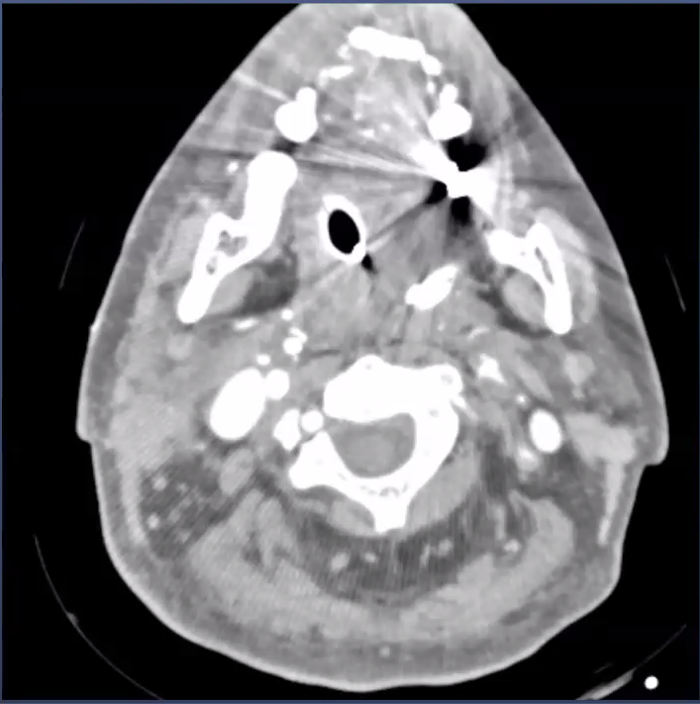

beam hardening due to contrast